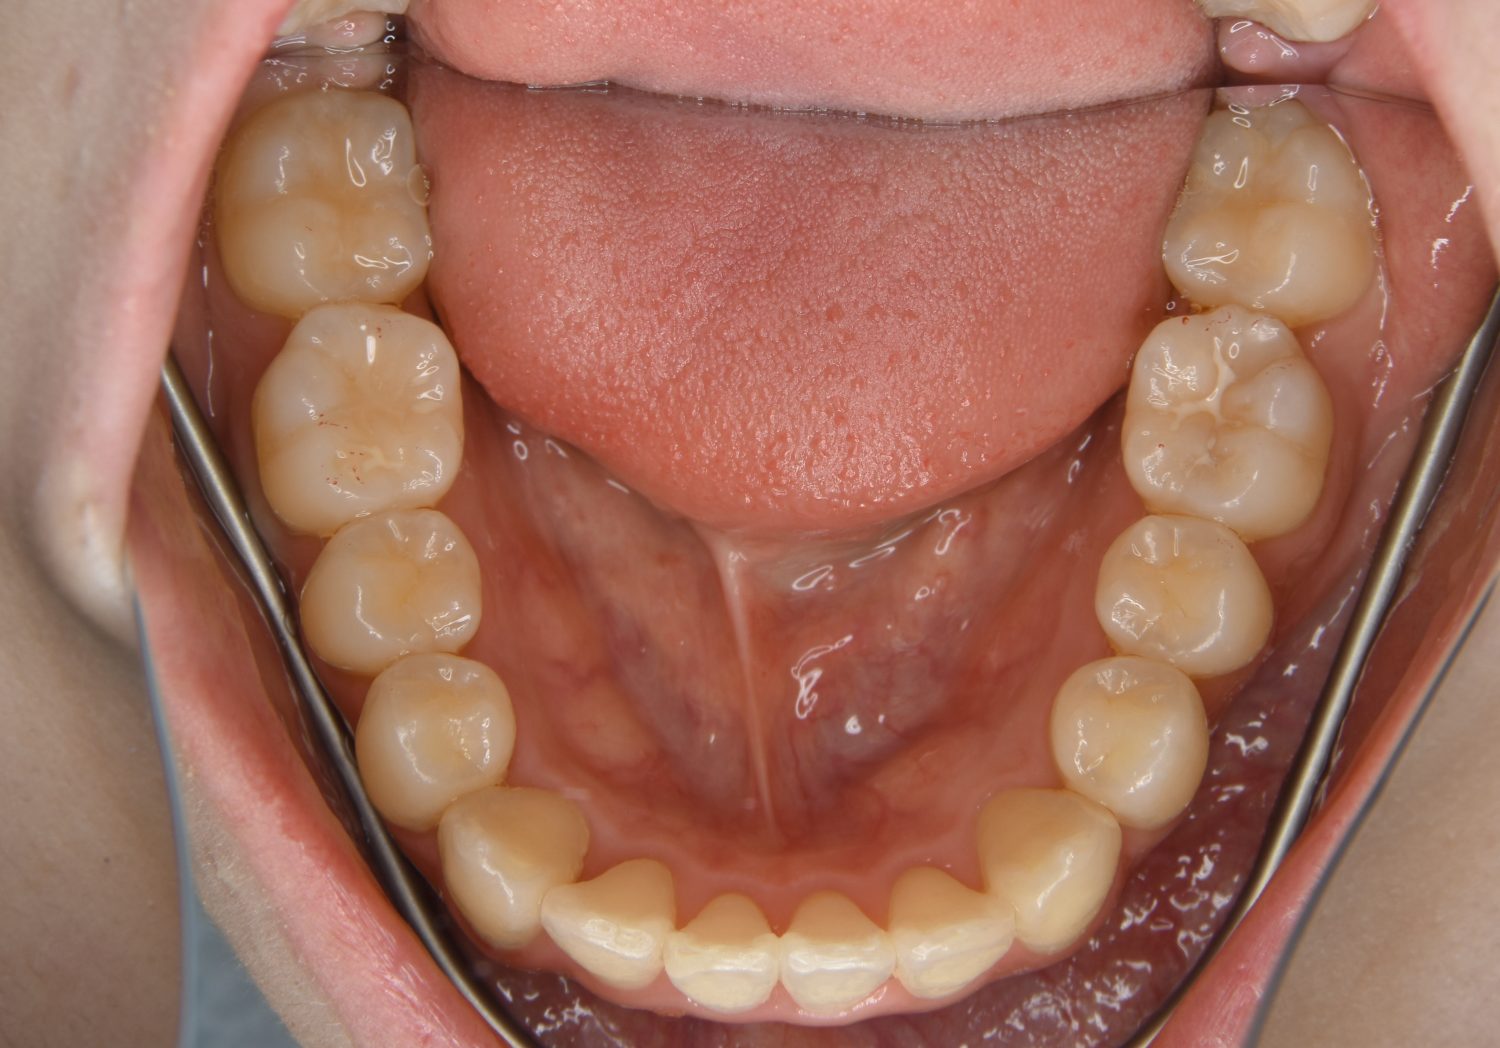

叢生の症例紹介②

Before

After

主訴

歯の凸凹を治したい。

治療内容

アライナー(インビザライン)にて非抜歯で治療を行いました。

上下前歯部に叢生(凸凹)が認められる状態でした。歯列の遠心移動を行うことで機能面および審美面が改善されました。